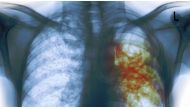

Beijing: China is experiencing its deadliest outbreak of the H7N9 bird-flu strain since it first appeared in humans in 2013, killing 79 people...